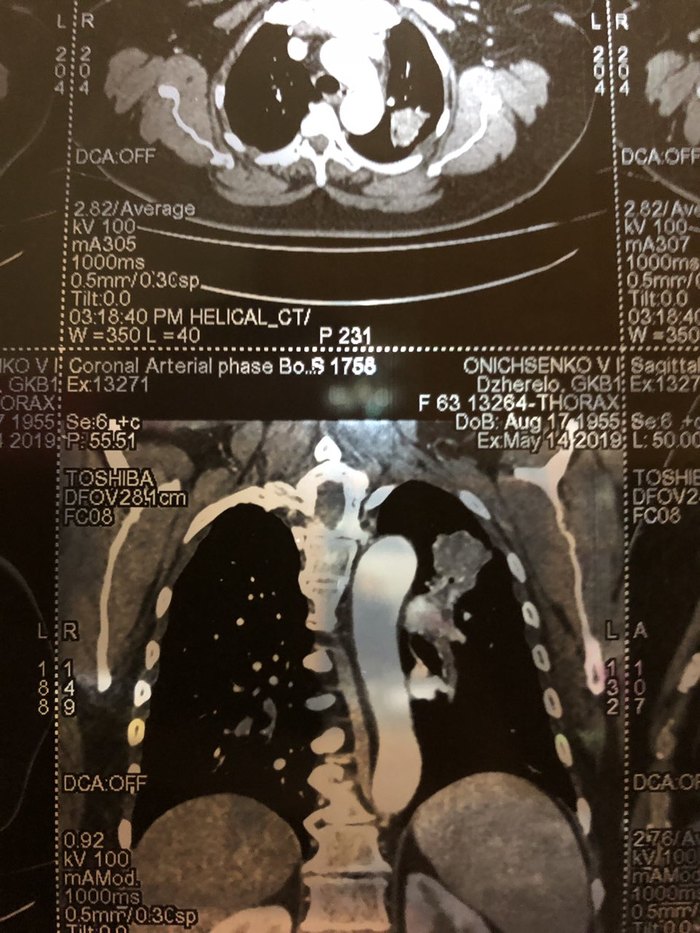

Рак легких

Друзья, мама не курила не пила , и вот такое вот у нее Ей 63  года, пока чувствует себя хорошо , но глядя на снимки я понимаю что это блин капец ( Помогите расшифроватьи объяснить сколько осталось  , завтра идем к врачу , боюсь с ней заходить , она не переживет когда узнает . Спасибо